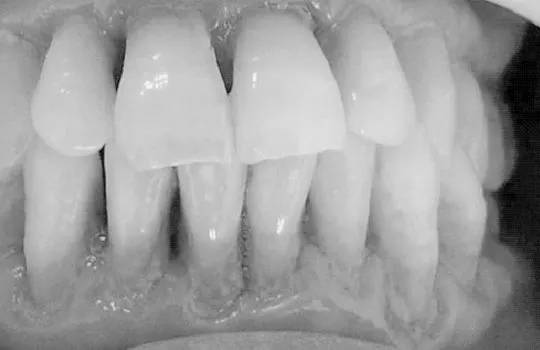

牙龈周围菌斑、牙结石大量堆积,细菌大肆滋生刺激牙龈,引发炎症,导致牙龈萎缩、牙齿松动、移位等问题,牙齿看上去就感觉像变长了。

成年人多少都患有牙周疾病,但因进展缓慢常常忽略,发现问题时已到“牙周病末期”了,虽然可以通过牙周治疗去除牙结石,缓解炎症,但萎缩的牙龈却再也找不回来了。

治疗:如果已经患了牙龈萎缩的朋友,需要尽早进行牙周刮治,将牙龈边的牙结石清除干净,虽然之前的牙龈很难救回来了,但防止它继续萎缩下去也是非常必要的。

长期横向拉锯式刷牙或用过硬牙刷、刷牙过猛都会导致牙颈部磨损,牙颈部是牙齿薄弱部位,因此耐磨能力_差,长期磨损消耗会引起牙龈萎缩,牙根暴露,让我们感觉牙齿变长了。